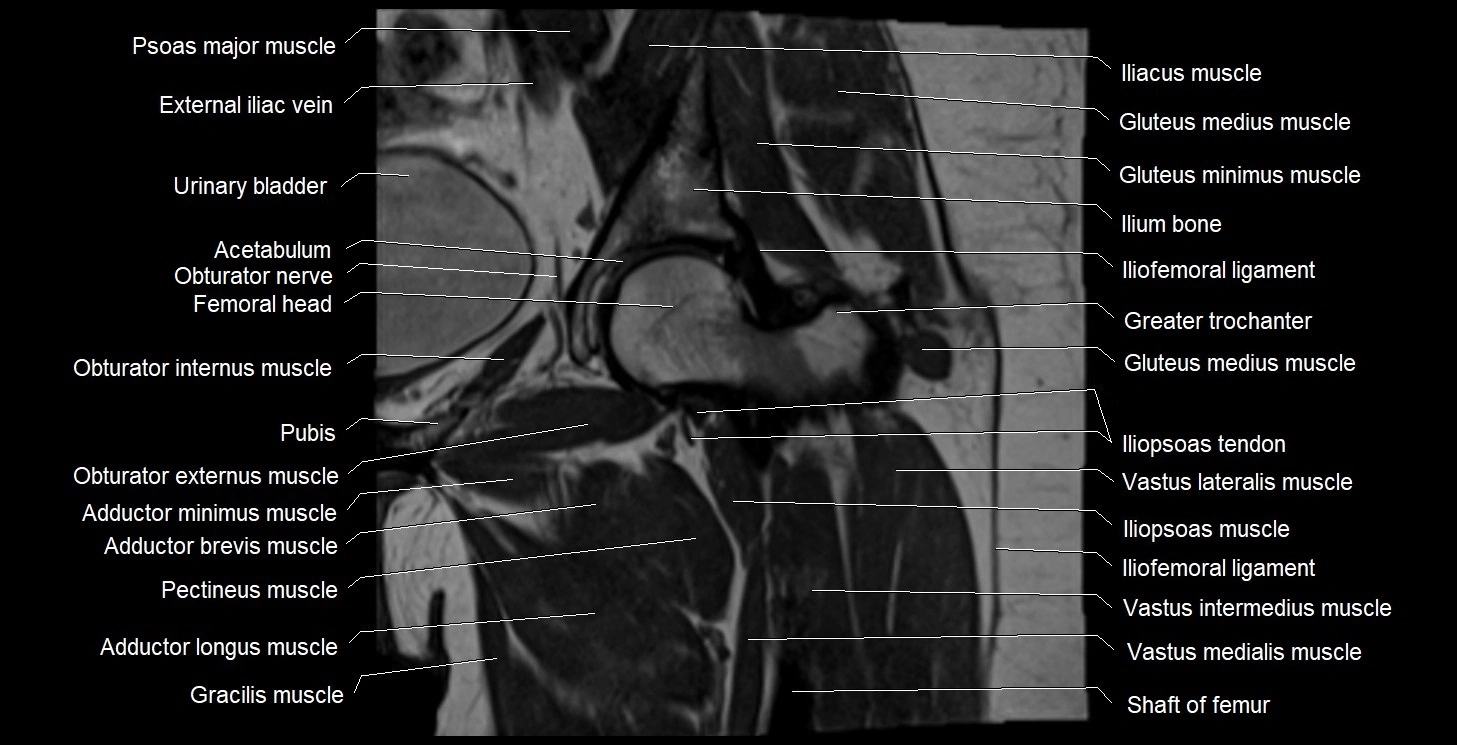

- Acetabulum

- Gluteus medius muscle

- Gluteus minimus muscle

- Gluteus minimus tendon

- Gracilis muscle

- Greater trochanter

- Head of femur

- Iliofemoral ligament

- Iliopsoas muscle

- Iliopsoas tendon

- Ilium bone

- Obturator externus muscle

- Obturator internus muscle

- Obturator nerve

- Pectineus muscle

- Psoas major muscle

- Pubic bone

- Rectus femoris muscle

- Urinary bladder

- Vastus intermedius muscle

- Vastus lateralis muscle

- Vastus medialis muscle

- Zona orbicularis ligament